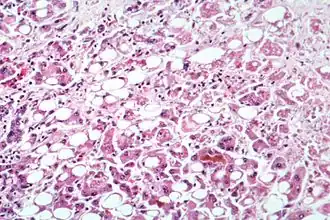

![]() Микрофотография клеток печени, поражённой алкогольным гепатитом | |